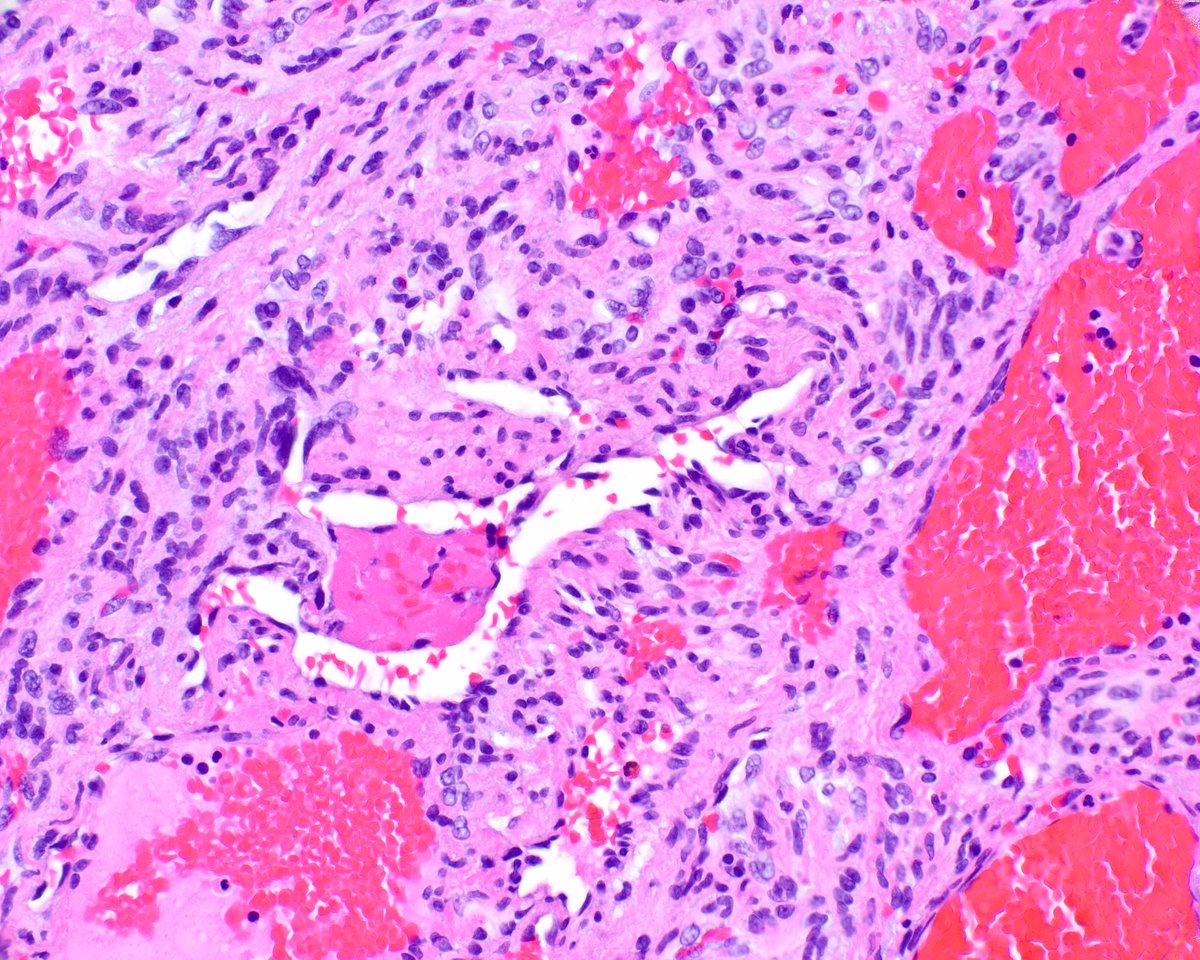

Lymphoepithelioma, spindle cell type (case I). The microscopic picture

Lymphoepithelioma, spindle cell type (case I). The microscopic picture Spindle Cell Epithelioma Here, we report 2 cases of spindle cell epitheliomas of the vagina. Spindle cell epithelioma is a very rare benign tumour of the vagina, which contains epithelial and mesenchymal components and. This lesion represents a benign spindle cell epithelioma (mixed tumor of vagina). Spindle cell epithelioma is a very rare benign tumour of the vagina, which. Electron microscopy of the. Spindle Cell Epithelioma.